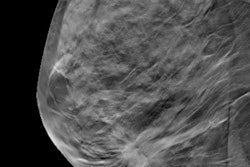

They enrolled 102 consecutive patients, each undergoing ultrasound/mammography-guided wire localization for their lesions followed by FFDM and DBT (both, Mammomat Inspiration, Siemens Healthineers). Two blinded radiologists independently analyzed the images and identified in which direction the lesion was closest to the specimen margin and measured the margin width.

The readers rated images from each modality for the presence or absence of the lesion within the specimen, lesion conspicuity, lesion type and features, lesion size, and identification of the direction in which the lesion is closest to the specimen edge. The readers' findings were corroborated by histopathological analysis.